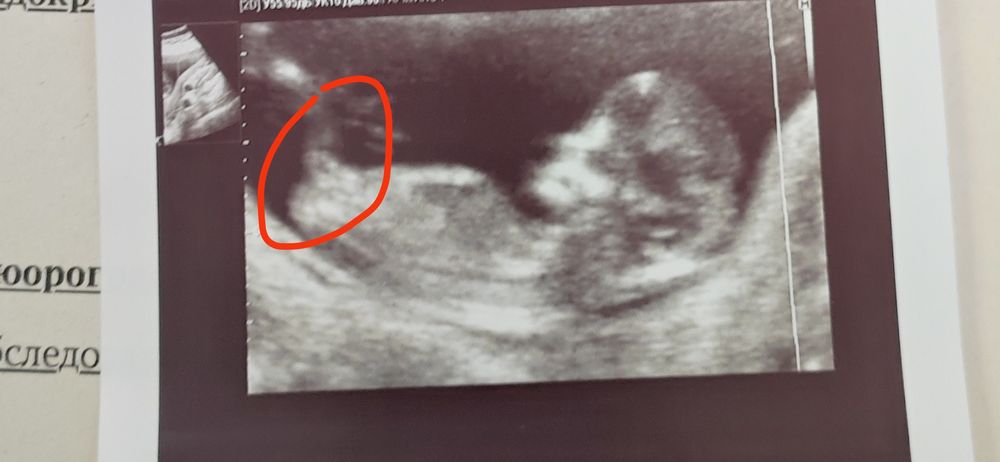

Может кто шарит по этим бугоркам половым , сегодня была на 1 скрининге, когда на мониторе врач показывал ребенка,то вроде как бугорок(если это был он) был параллельно расположен, а вот по фото будто вверх немного торчит ,если конечно я его не путаю с чем то другим ,вот фото ,что думаете ?)

По-моему, это нога, судя по размеру/соотношению к телу 😅

Вообще нам врач смотрел с другого ракурса - как бы снизу между ножками. На сроке 12 недель там всё было прекрасно видно - с девочкой не ошиблись.

Фантазирую, что бугорок - это просто ножка, которую он подсогнул..)

А что врач говорит?)